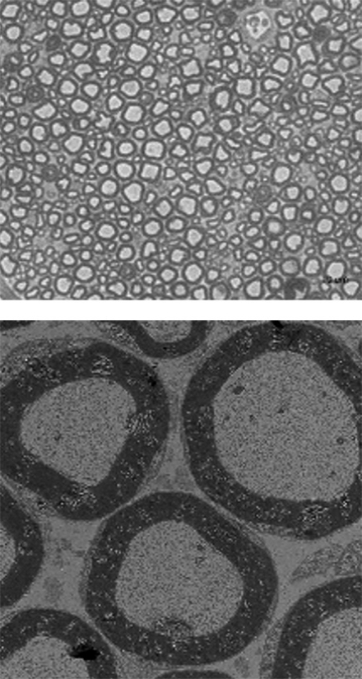

정상 쥐모델

-

샤르코-마리-투스 쥐모델

EN001 투여

신경을 감싸고 있는 수초(지질단백)은 사진에서 짙은 회색으로 표시가 되는데

정상 쥐모델보다 CMT 쥐모델에서 수초의 두께가 얇아지고 형태가 불안정한 것을 볼 수 있습니다.

그러나 EN001을 샤르코-마리-투스 쥐모델에 투여하였을 때, 수초의 두께가 두꺼워지고 형태가 건강해진 것을 관찰하였습니다.